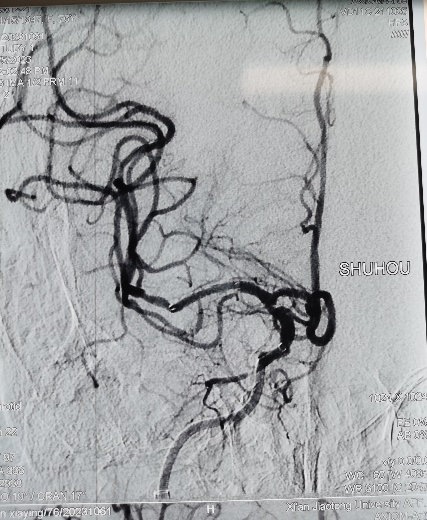

右侧大脑中动脉闭塞再通术后